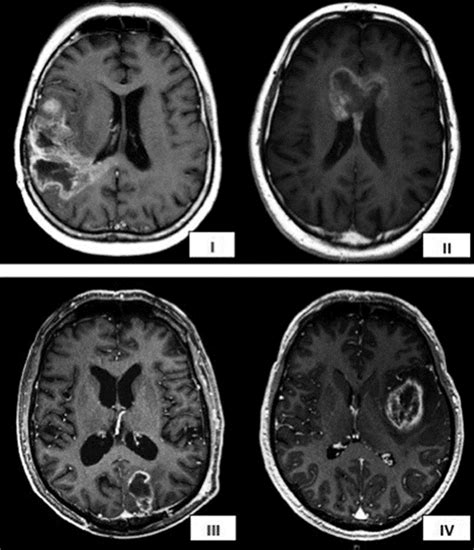

Recurrence of GBM. AC Contrastenhanced MRI of a patient with GBM in